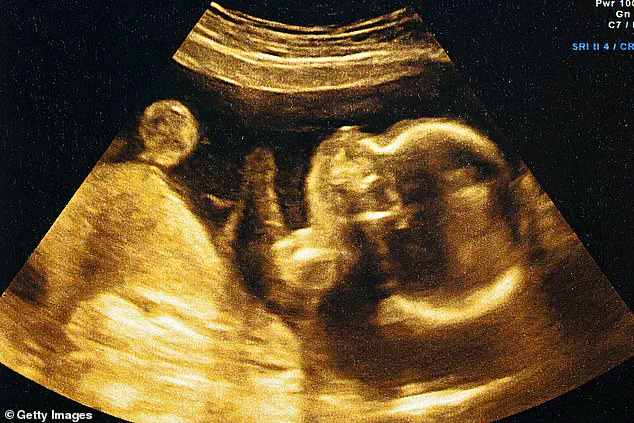

The new AI-driven approach, developed by researchers at the University of Kentucky, leverages machine learning algorithms trained on an extensive dataset of over two million ultrasound images collected between 2017 and 2020.

The software, named Ultrasound AI, analyzes fetal measurements and other visual cues from ultrasound scans to predict gestational age and birth timing.